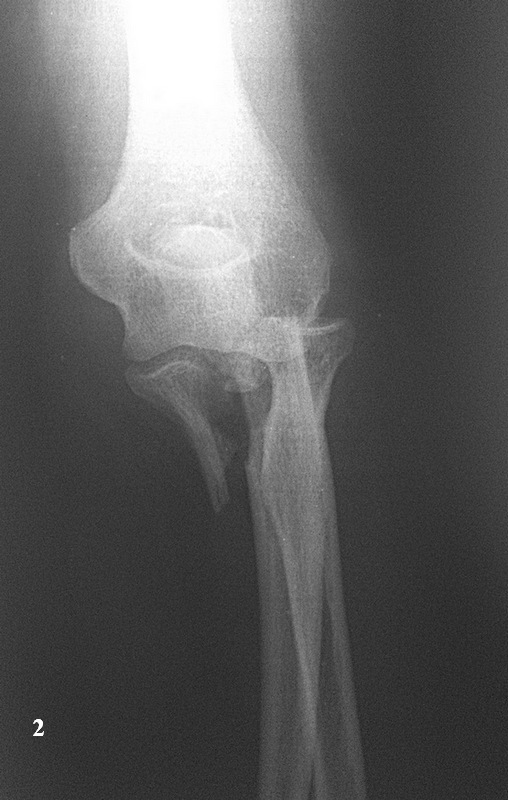

Хочу попросить совета у сообщества по поводу следующего клинического случая. Женщина, 65 лет. Закрытый перелом Монтеджи слева в октябре 2013 года. (рис. 1, 2). Для наглядности сделал скиаграмму перелома (рис. 3, 4). На 8-е сутки накостный остеосинтез пластинами с угловой стабильностью. Головка луча была восстановлена из отломков (рис. 5) и собрана на спицах одну из которых скусили и оставили под пластиной.(рис. 6). Вроде получилось стабильно, видео на операции по этой ссылке: